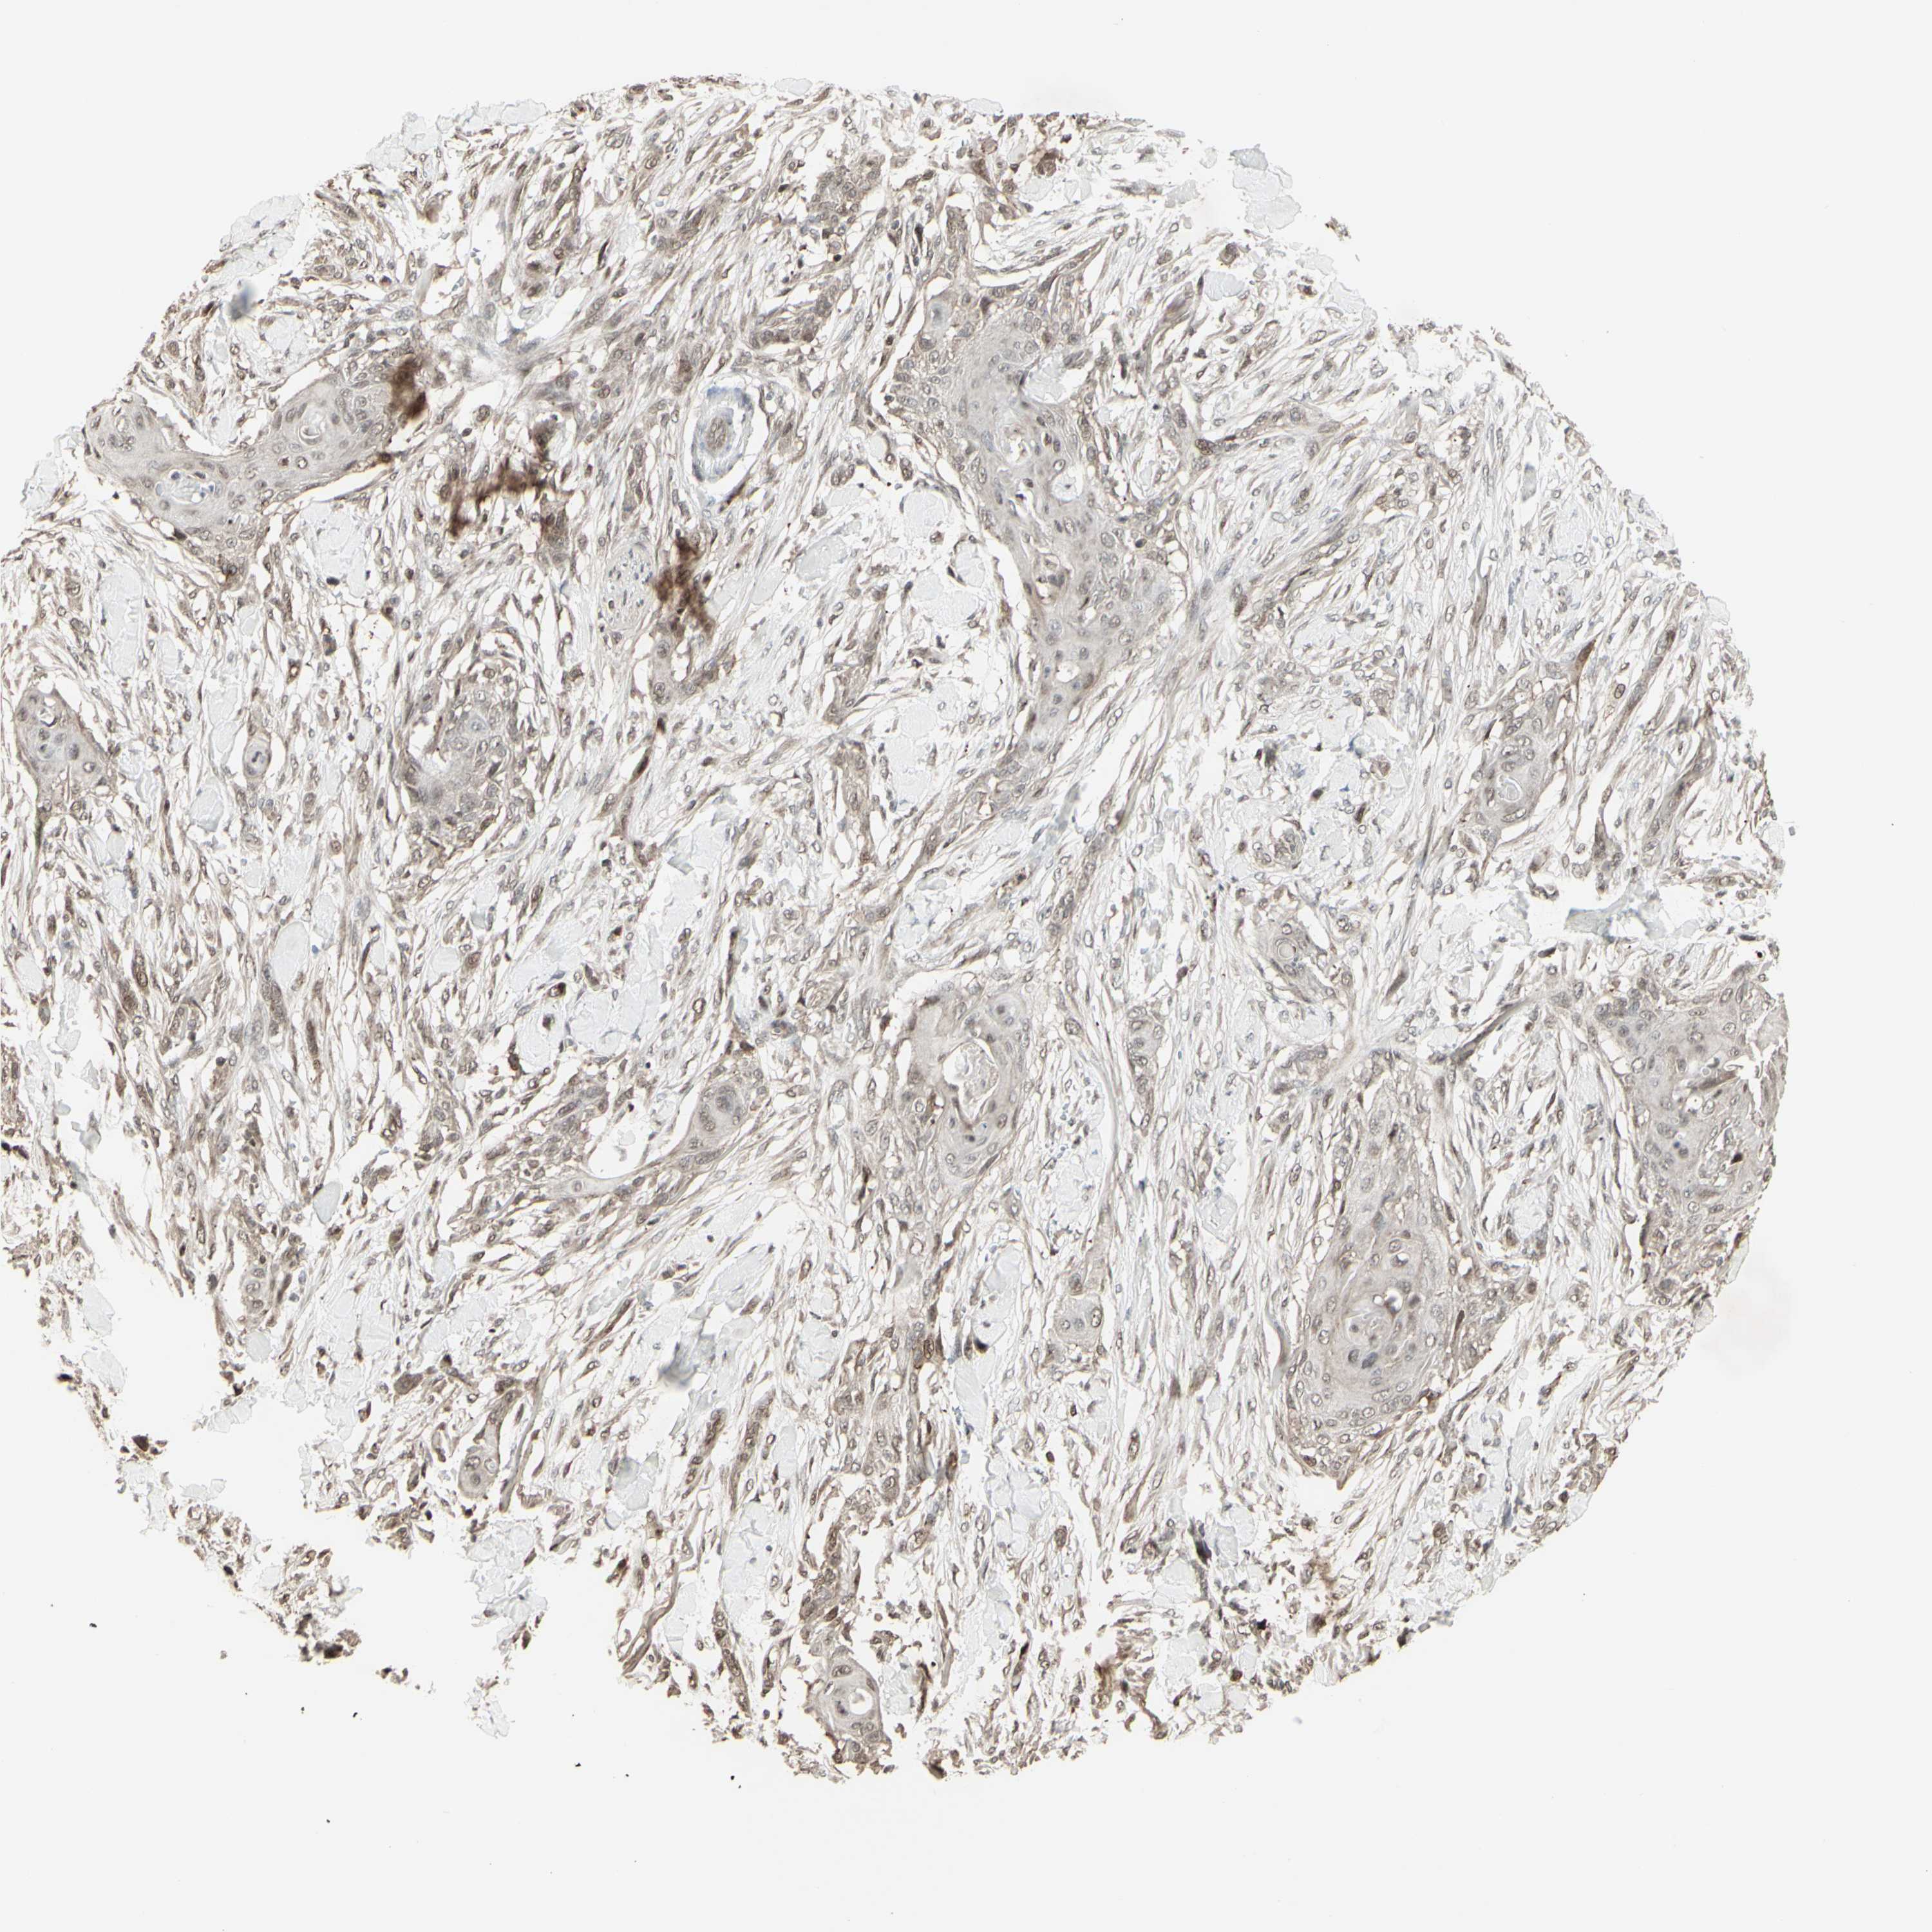

Basal cell and squamous cell cancer

SKIN CANCER - Protein expressioni

A mouse-over function shows sample information and annotation data. Click on an image to view it in a full screen mode. Samples can be filtered based on level of antibody staining by selecting one or several of the following categories: high, medium, low and not detected. The assay and annotation is described here.

Antibody stainingi

Antibody staining in the annotated cell types in the current human tissue is reported as not detected, low, medium, or high, based on conventional immunohistochemistry profiling in selected tissues. This score is based on the combination of the staining intensity and fraction of stained cells.

Each image is clickable and will lead to virtual microscopy that enables deeper exploration of all samples and also displays staining intensity scores, fraction scores and subcellular localization as well as patient and tissue information for each sample.

Antibody CAB011442

Basal cell carcinoma

Squamous cell carcinoma, NOS

Squamous cell carcinoma, metastatic, NOS

Papilloma, NOS